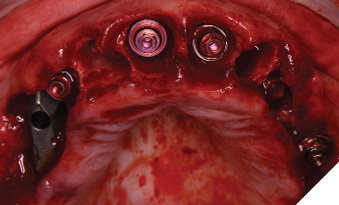

Treatment phase: The patient requested that we treat the maxilla first followed by the mandible. The surgical visit included the following treatment. Extraction of teeth 2,7,8,9,15 and removal of implants 5 and 13. Implant 14 was kept due to its good bone support and favorable prognosis (Figs. 6A, 6B). Computer guided surgery (Keystone – Contra Angle Guidance System) with a surgical guide was utilized to perform all osteotomies and place the dental implants (Figs. 7A, 7B).

Implants were placed in tooth positions 4,6,8,9 and 12 (Genesis Active – Keystone Dental). Allograft bone grafts (Dynacore – Keystone Dental) were placed into all extraction sockets and intraboney defects. Multiunit abutments were inserted and torqued to 30ncm (Figs. 8A, 8B). All soft tissues were sutured. Nexus scan gauges (Osteon Medical KDG) were placed on the multiunit abutments and iOS impressions were taken (Figs. 9, 10). The pretreatment virtual wax-up was integrated to the actual implant positions using prosthetic design software (Exocad) and the provisional restoration was 3D printed (Figs. 11A, 11B).

Fig. 8A

Fig. 8B